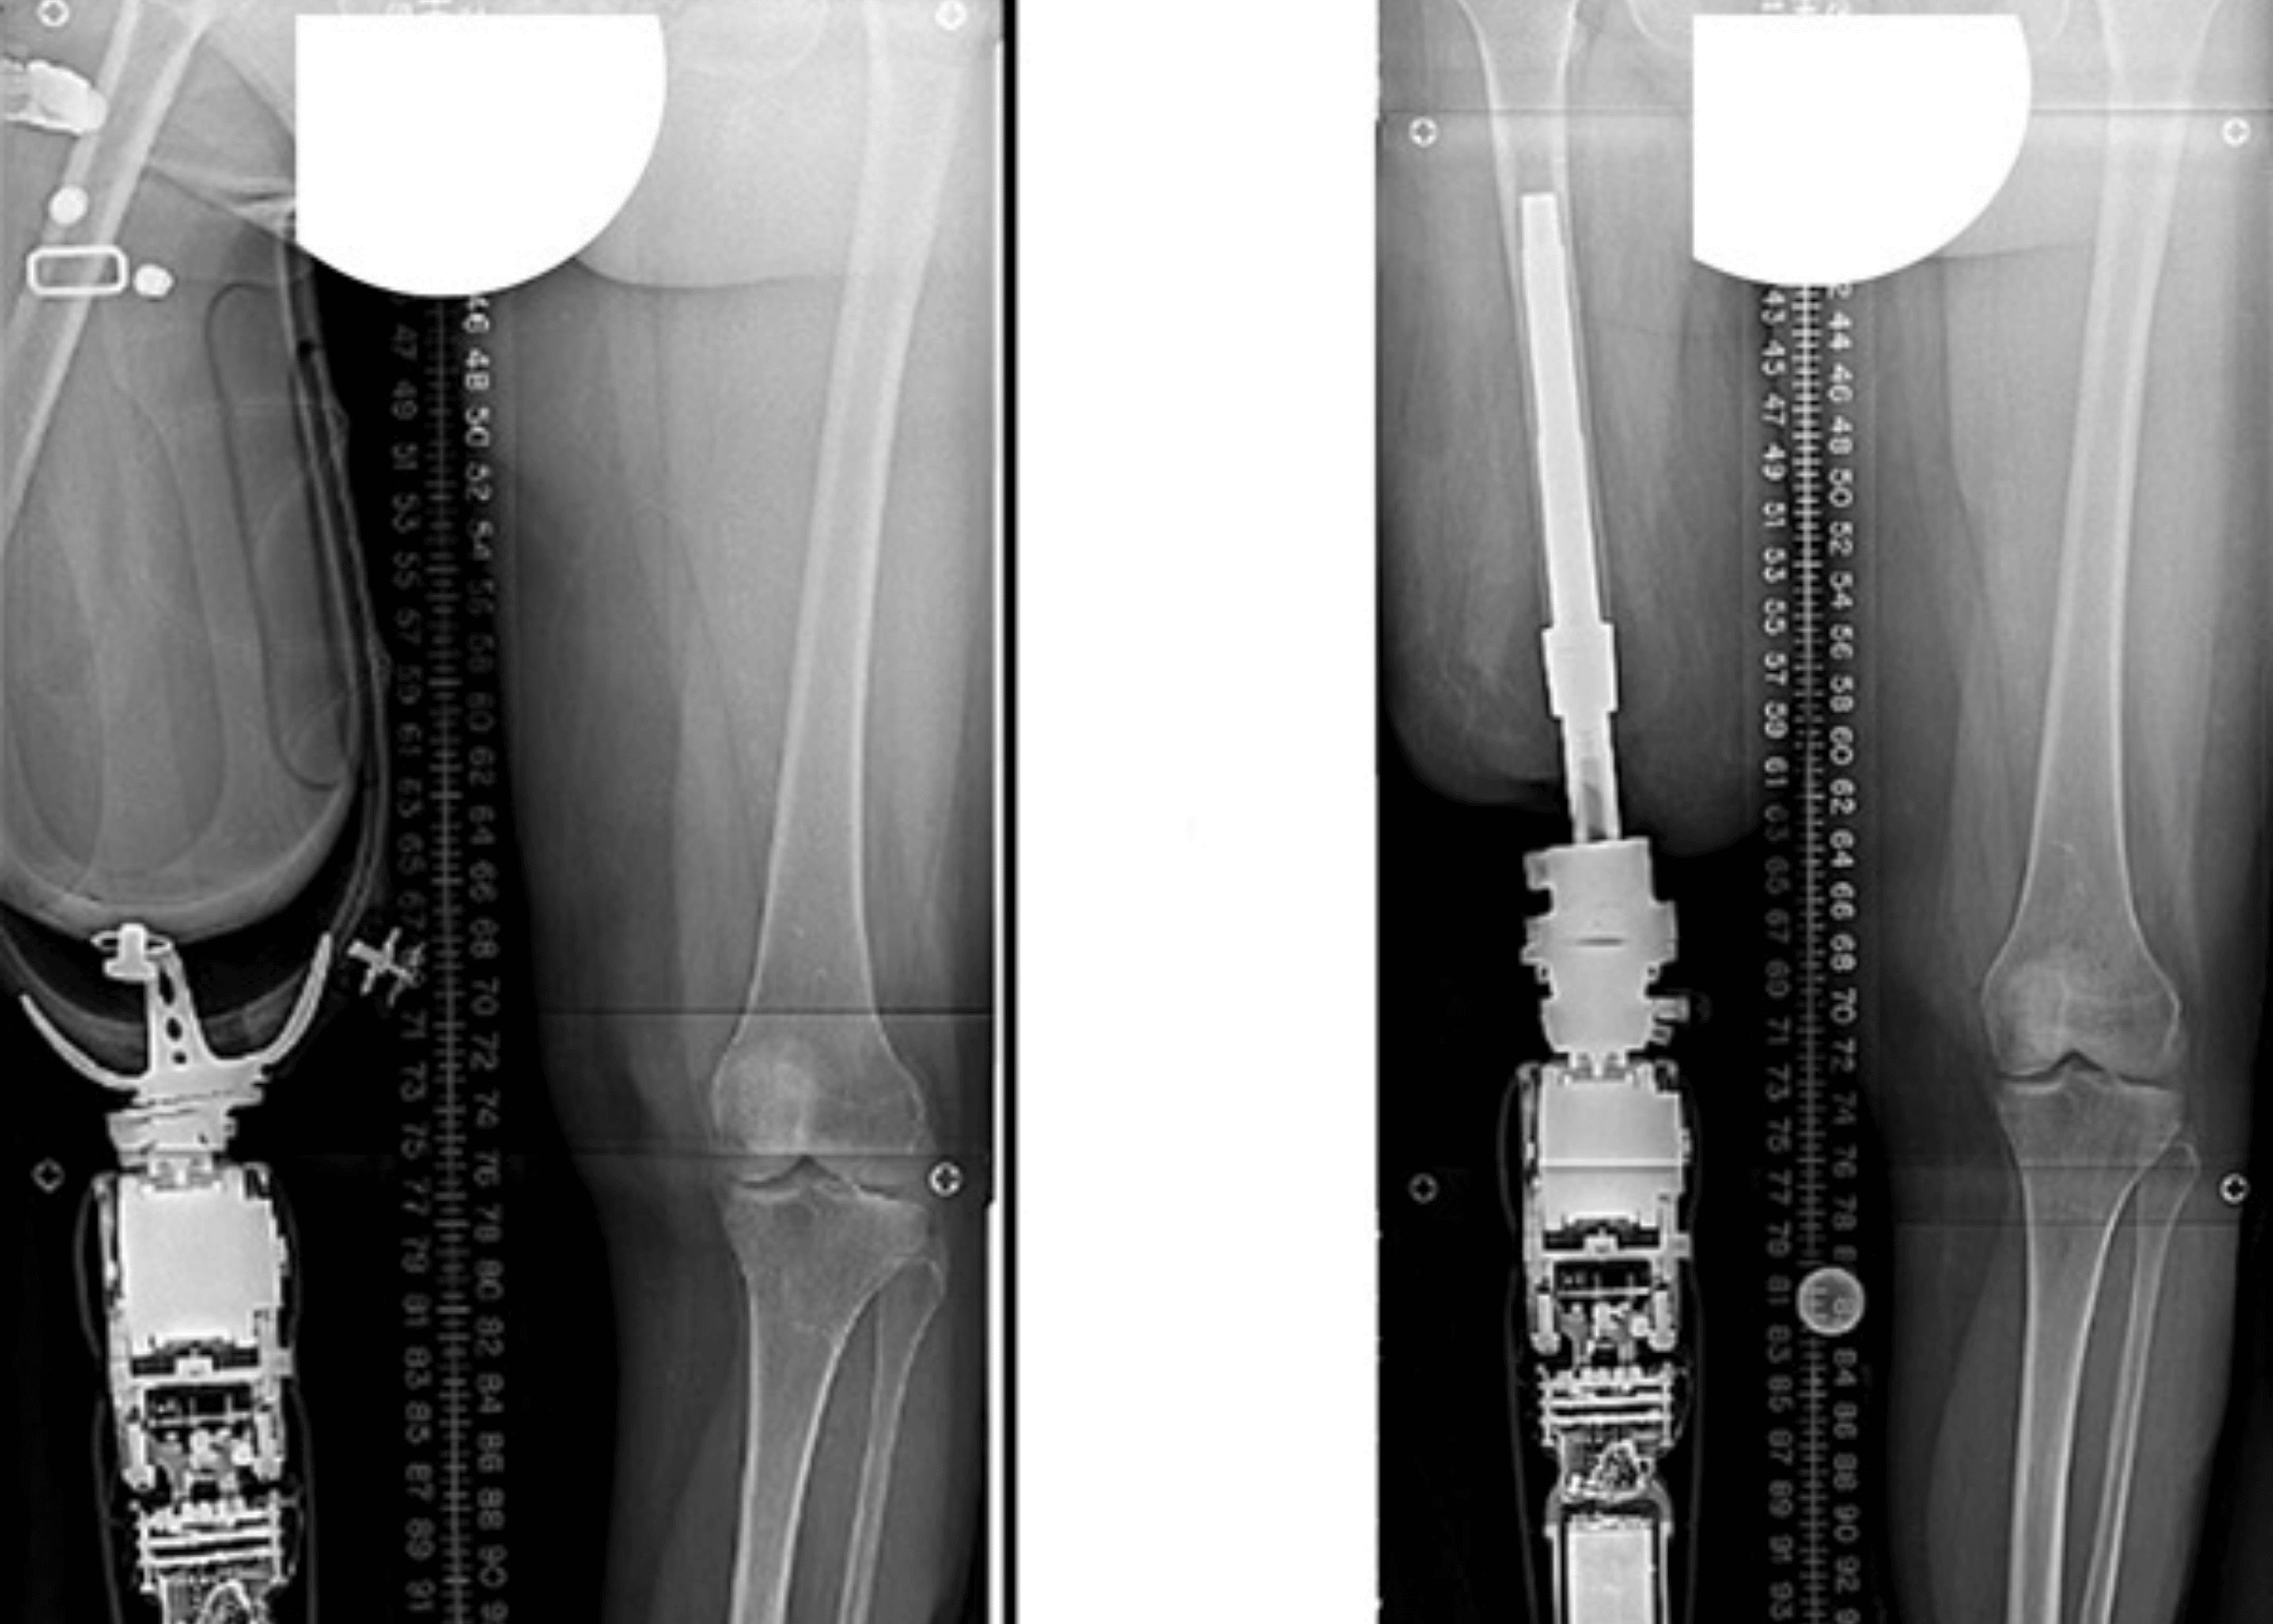

Pioneering Osseointegration Surgery Transforms Life for Transtibial Amputee

Introduction Burjeel Medical City continues to lead the way in advanced surgical